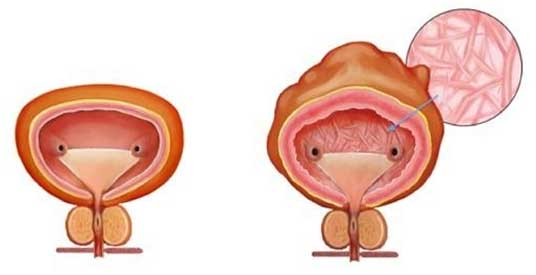

Κύστη “προσπαθείας”

Στην πραγματικότητα, ο προστάτης μεγαλώνει, αλλά η κύστη υποφέρει, αφού δική της ευθύνη είναι τόσο η αποθήκευση των ούρων, όσο και η αποβολή τους, δηλαδή η ούρηση.

Η αποφρακτική ούρηση οδηγεί αρχικά στην υπερτροφία του εξωστήρα μυ της κύστης που προσπαθεί να αντιρροπίσει τις υψηλές ουρηθρικές αντιστάσεις, ενώ στη συνέχεια θα εμφανισθούν δοκίδωση της κύστης και εκκολπώματα.

- Η επιμένουσα απόφραξη θα καταλήξει σε μία ουροδόχο κύστη λεπτή και ατροφική με μικρή δυνατότητα σύσπασης για την αποβολή των ούρων.

Ιστολογικά παρατηρείται ελάττωση των λείων μυϊκών ινών και αντικατάστασή τους με ίνες κολλαγόνο, που ελαττώνουν την διατασιμότητα της κύστης και συνεπώς την χωρητικότητά της.

Την τελευταία δεκαετία υπάρχει ιδιαίτερο ενδιαφέρον για τη μέτρηση του πάχους του τοιχώματος της κύστης που αποτελεί μία έμμεση μέτρηση της μάζας του εξωστήρα μυός. Οι υψηλές εξωστηριακές πιέσεις κατά την ούρηση σε άνδρες με υποκυστικό κώλυμα οδηγούν αρχικά σε αύξηση του μεγέθους του λείου μυός (υπερτροφία/υπερπλασία του εξωστήρα) που θα εξελιχθεί σε μείζονες μεταβολές σε πιο προχωρημένα στάδια, όπως ίνωση, υπερλειτουργικότητα και ελαττωμένη λειτουργική χωρητικότητα.